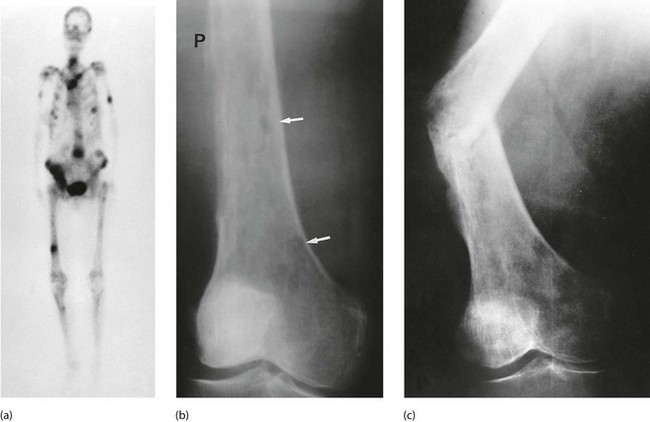

About two-thirds of breast cancer patients now survive for at least 20 years, but many eventually succumb from micrometastatic disease which later progresses to clinically evident metastases. Once metastases have appeared, treatment is palliative, but very worthwhile prolongation of life and improved quality of life can often be achieved. The commonest sites for metastases are bones, liver, lung and brain. Bone metastases are more likely in postmenopausal women with well-differentiated, ER-positive tumours. More than 90% of patients with metastatic disease have bone lesions. These are usually lytic and commonly affect ribs and vertebrae. They are very painful and can lead to pathological fractures (Fig. 45.17). Luckily, they often respond to palliative radiotherapy. Lobular carcinoma can metastasise to unusual sites such as skin (Fig. 45.18) and gastrointestinal tract.